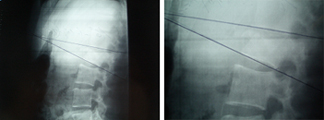

Técnicas 2

Imagen de la fractura y del postoperatorio con una reducción anatómica

y una visión de la espalda de la paciente con incisiones puntiformes

a las 48 horas de la intervención, en el momento de recibir el alta.